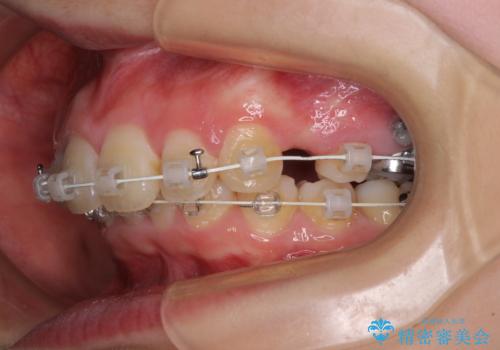

上顎前突を改善するために上顎左右第一小臼歯を抜歯し、補助装置を用いて上顎臼歯が前方に移動しないように工夫しながら、表側のワイヤー装置にて歯列を整えていくこととしました。

矯正治療後には、上顎欠損部をオールセラミックブリッジにて補綴治療を行うこととしました。